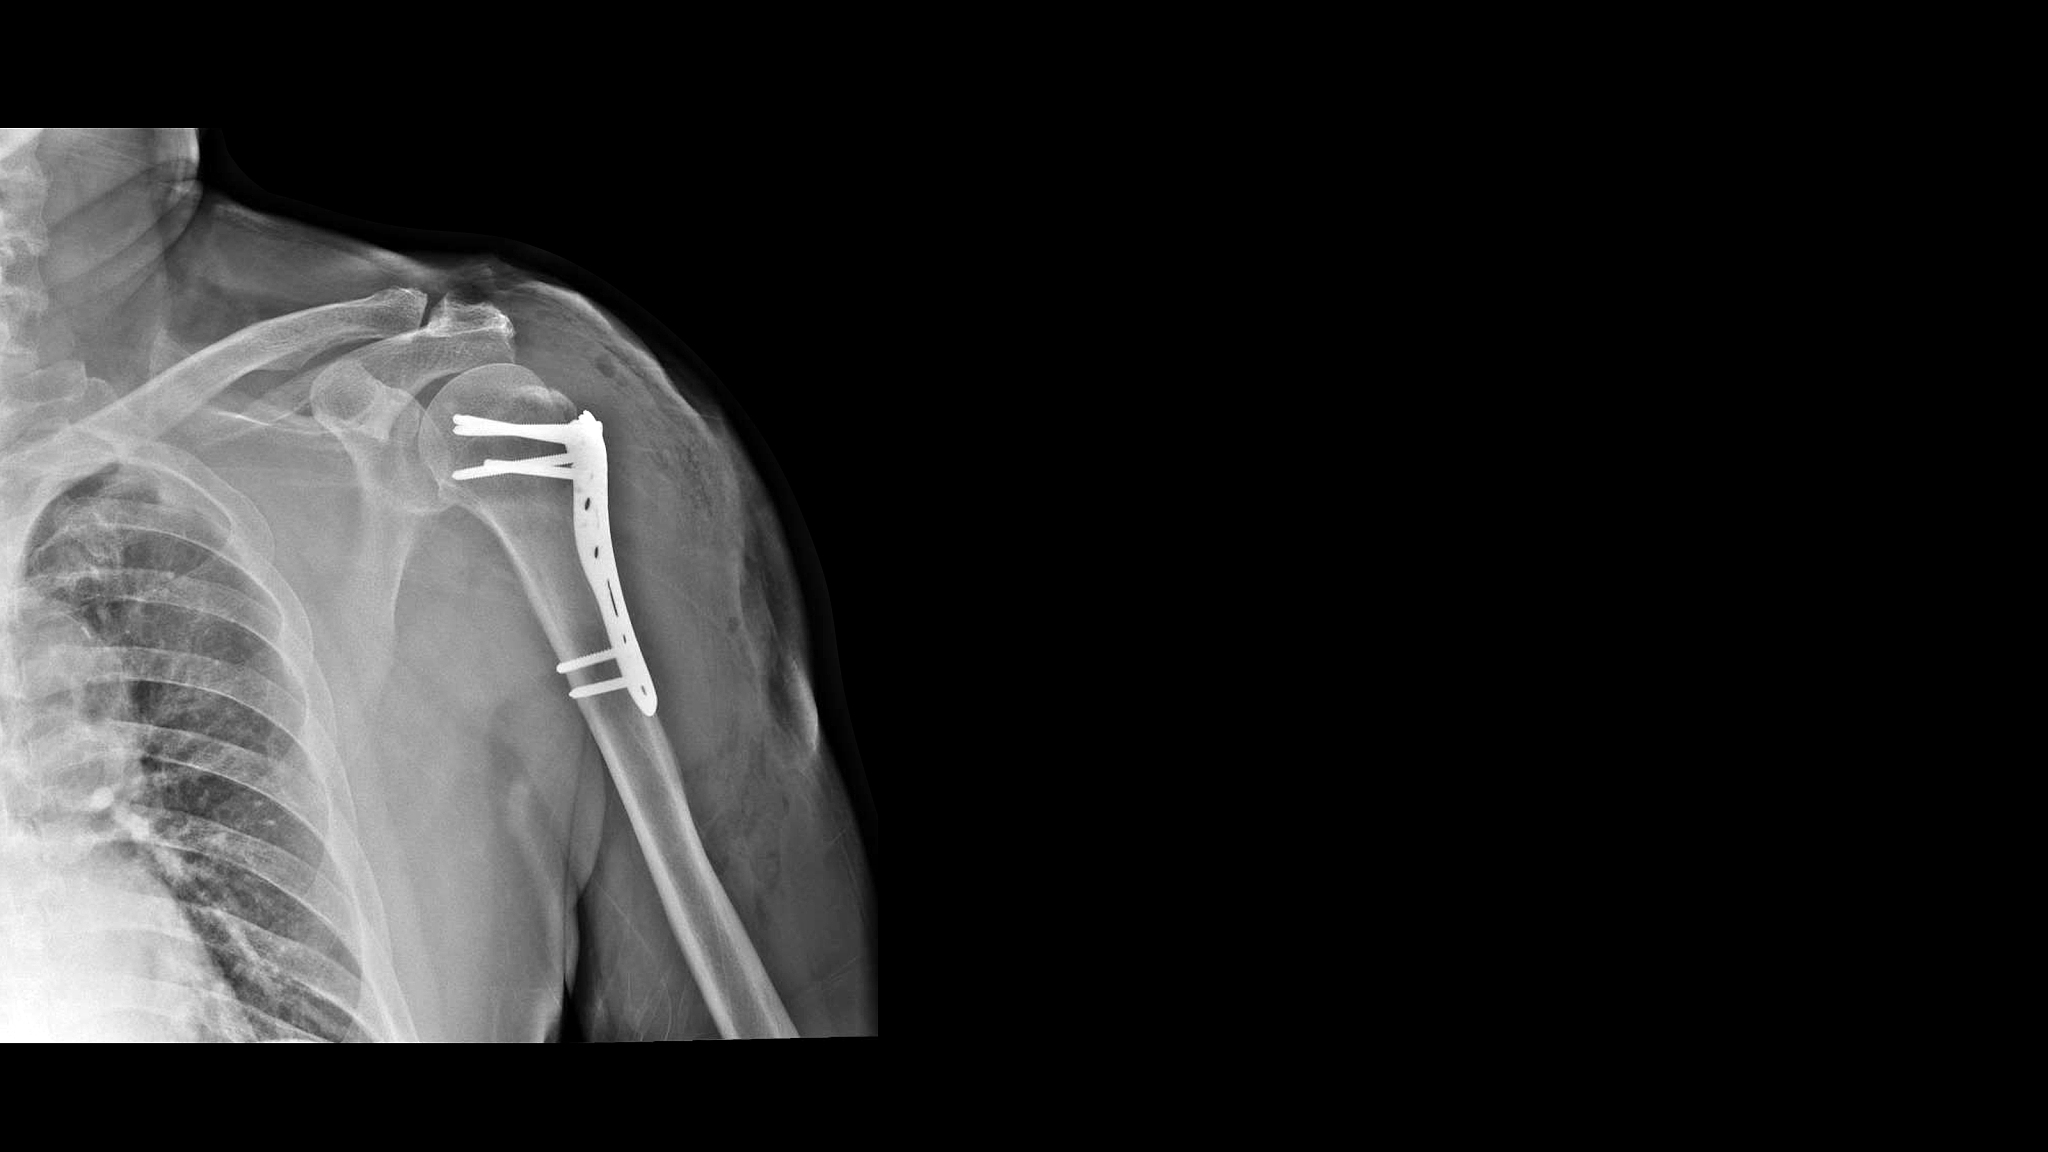

6. 手术治疗:如果非手术治疗无效,严重的肩周炎可能需要手术干预,如肩袖修复手术或关节镜手术。